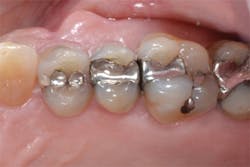

Figure 13: View of teeth Nos. 4 and 5 after curing the final occlusal layer of TPH Spectra composite.

Figure 14: Final restorations on teeth Nos. 4 and 5.